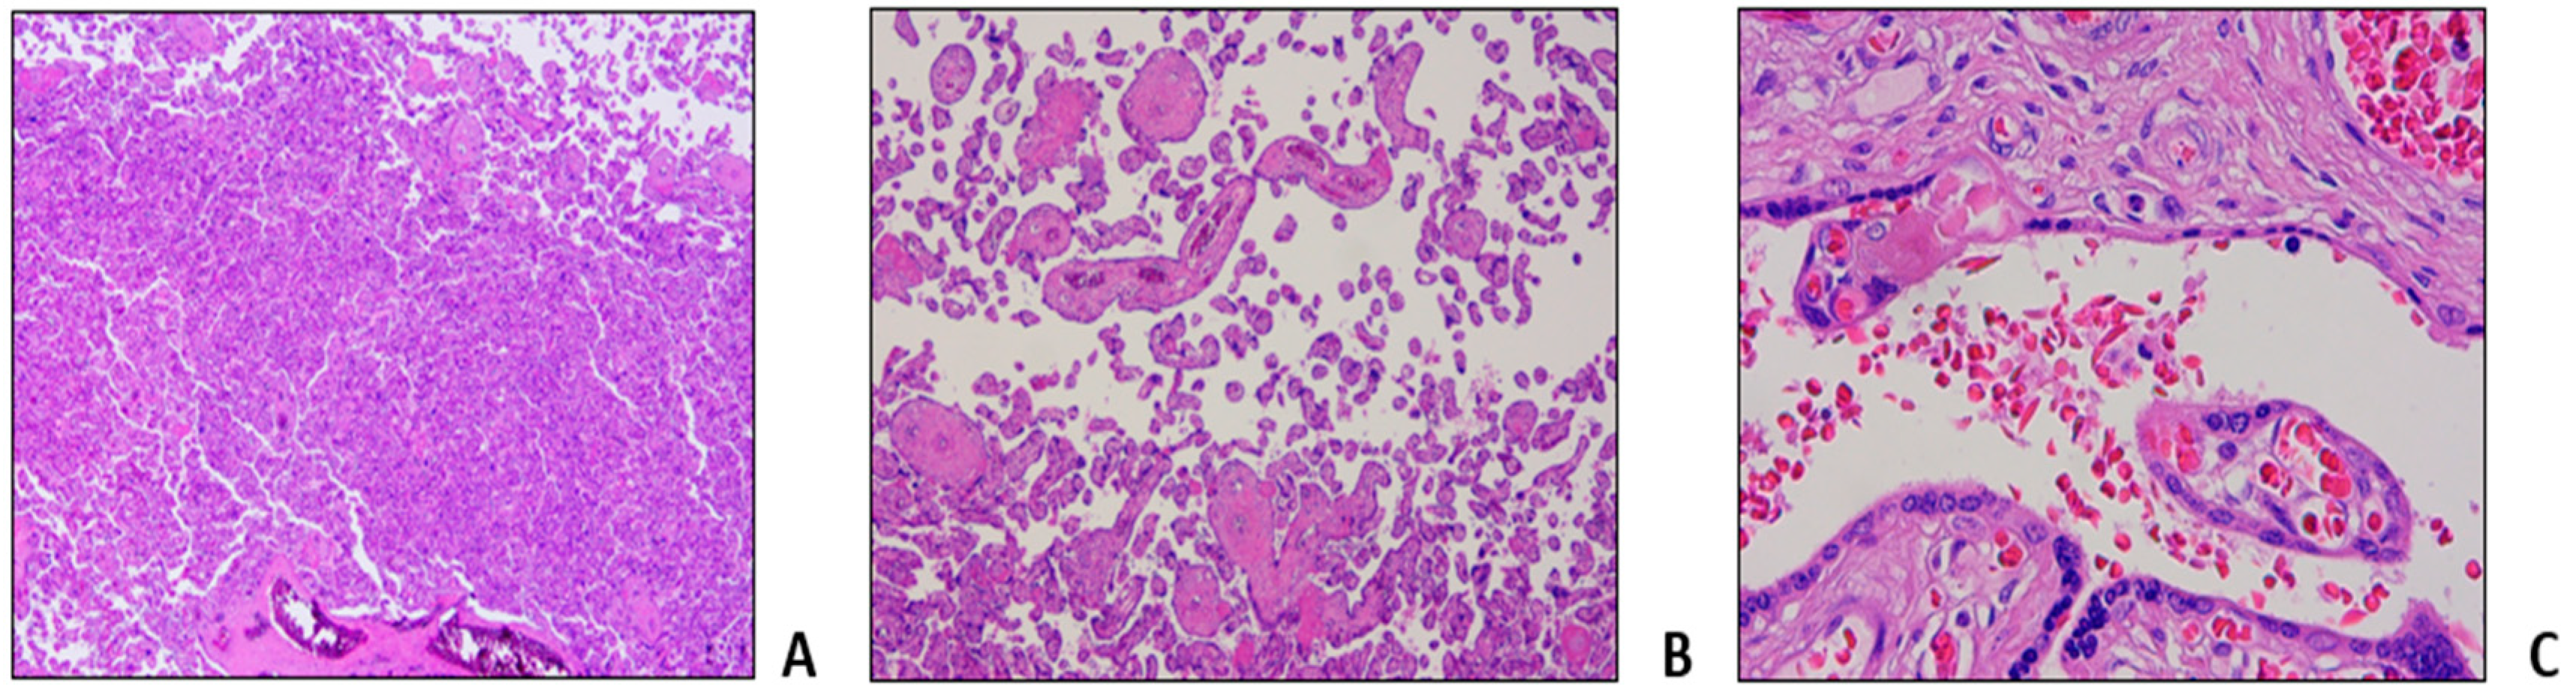

- Malinowski, A.K.; Dziegielewski, C.; Keating, S.; Parks, T.; Kingdom, J.; Shehata, N.; Rizov, E.; D'Souza, R. Placental histopathology in sickle cell disease: A descriptive and hypothesis-generating study. Placenta 2020, 95, 9–17. [Google Scholar] [CrossRef] [PubMed]